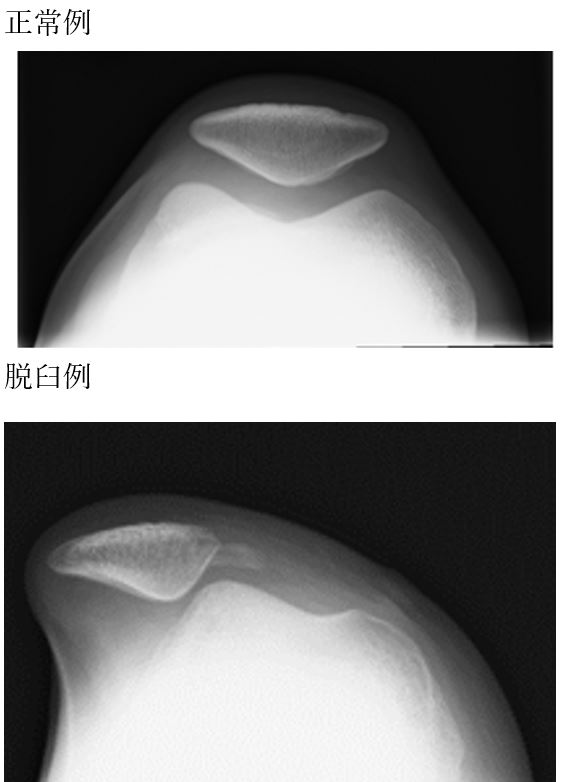

膝蓋骨脱臼は通常、膝がまっすぐで下腿がねじれた状態から膝が外側に曲った際に発生する。時に、膝が曲がった状態で膝蓋骨を強打することによって発生することもある。一般的に関連付けられているスポーツには、サッカー、体操、アイスホッケー、などがあげられる。ほとんどの脱臼は、常に正中線からずれて発生する。診断は通常、症状に基づいて行われ、X線によって確認される。